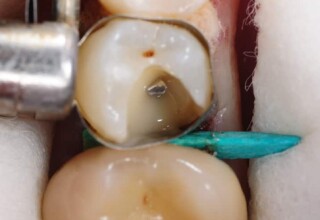

Αποκατάσταση Ραγισμένου Γομφίου με σφράγισμα Σύνθετης Ρητίνης

Τα ραγισμένα δόντια αποτελούν μια πρόκληση για την επανορθωτική οδοντιατρική από την άποψη της δυσκολίας της αποκατάστασης(συνήθως μεγάλα σφραγίσματα) άλλα κυρίως από τα προληπτικά μετρά που πρέπει να παρθούν για να αποφευχθεί ένα πλήρες κάταγμα. Η ακόλουθη περίπτωση παρουσιάζει την απλούστερη προσέγγιση της άμεσης συγκολλούμενης αποκατάστασης από σύνθετη ρητίνη. Βασίζεται στο σκεπτικό ενός συγκολούμμενου σφραγίσματος που «κρατάει» τα εναπομείναντα οδοντικά τμήματα «ενωμένα». Ο συγκεκριμένος γομφίος παρέμεινε ακέραιος για δυο χρονιά, οπότε χρειάστηκε απονεύρωση γιατί νεκρώθηκε και κατόπιν τοποθετήθηκε στεφάνη για αυξημένη προστασία.